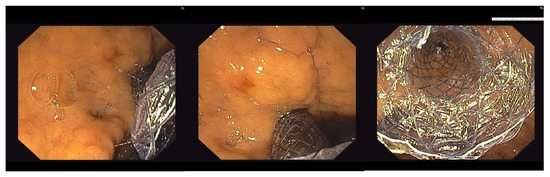

Once stable position with the guidewire was achieved, the next step was dilation of the fistulous tract. A 6fr cystotome (Endo-flex GmbH, Voerde, Germany) paired with electrosurgical unit ERBE Vio 300D (Erbe Elektromedicin Gmbh, Tübingen, Germany) set at Endocut I (effect 2, cut duration 3, cut interval 3) was used. With the cystotome in the bile ducts, further contrast injections or guidewire manipulations could be easily performed if necessary. Eventually, an SEMS was inserted to create a transmural tract between the left hepatic bile ducts and the stomach. Two type of SEMSs were used. Initially fully covered-SEMSs (FC-SEMS) (WallFlexTM; Boston Scientific; Marlborough, MA, USA) 10/80 mm or 10/100 mm were utilized. Subsequently, a dedicated SEMS for hepatico-gastrostomy (Hanarostent BPE, M.I. Tech, Pyeongtaek, Korea) 10/80 mm was used as standard. The stent was positioned in such a way as not to obstruct side biliary branches and to protrude at least 2 cm in the stomach. Eventually, contrast injection through the stent was performed to confirm its patency and lack of leakage in the peritoneal cavity. Different stages of EUS-HGS are illustrated in Figure 2 and Figure 3.

Figure 2. Stages of EUS-HGS: (A) Puncture of a dilated left-sided bile duct; (B) tract dilation with a 6fr cystotome; (C) stent insertion under fluoroscopic guidance.

Figure 3. Endoscopic view of the distal part of the stent in the stomach.